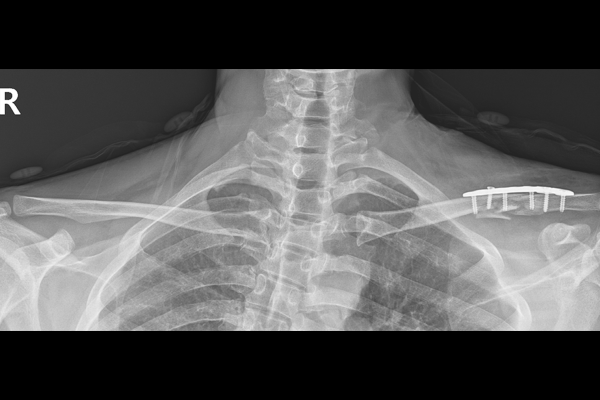

경기도 양주 옥정에 거주하시는 40세 남성 환자분께서 좌측 쇄골 골절 증상으로 내원해주셨습니다. 환자분께서는 내원 전날 화장실에서 넘어지며 어깨쪽을 강하게 부딪쳤고, 급하게 응급실을 갔을 때 골절 소견과 수술 권유를 받으셨다고 말씀하셨습니다. 이후 수술적 치료를 위해 골절 수술 경험이 많고 잘 하는 의료기관을 찾아보시던 도중 저희 병원을 알게되시어 찾아오시게 되었다 하셨습니다.

20ac6334118c27e0cf78b5d1504f202d_1767861870_4217.png

지참해오신 X-RAY 사진을 확인해보니, 좌측 쇄골뼈가 분쇄 골절 되어 아예 어긋나 있는 것을 확인하여 좌측 쇄골 분쇄 골절(Comminuted Fx. clavicle shaft Lt.)을 진단하였습니다.